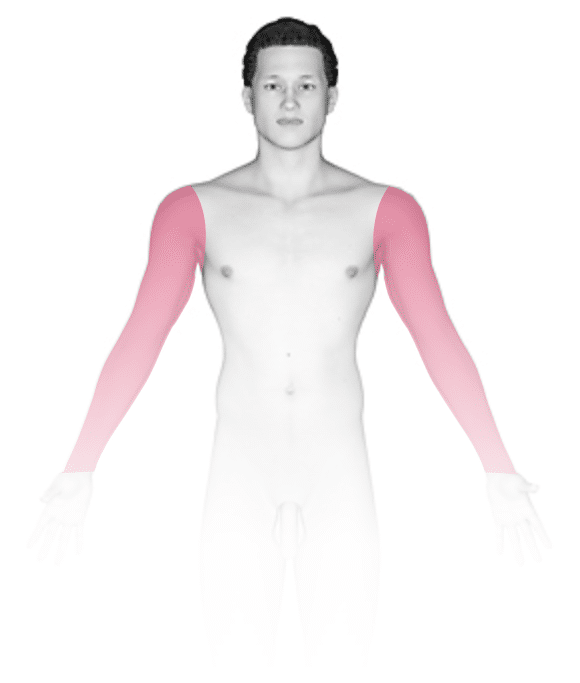

The most common locations for pityriasis alba include:

- Shoulders, upper chest, and upper arms

Pityriasis alba appears as several (2–20) light-colored (hypopigmented) patches ranging in size from 1–4 cm. The patches may have slight and subtle surface patches (scale). Occasionally, the condition begins as mildly itchy, pink patches that develop into lightened patches of skin.